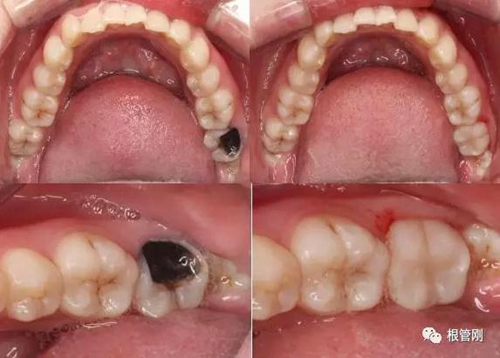

這是一顆嚴(yán)重的蛀牙,顏色發(fā)黑,牙齒的一半已經(jīng)崩解,看到此情此景,也許很多人會(huì)想它的神經(jīng)肯定死掉了吧?它還有救嗎?應(yīng)該會(huì)做根管治療+牙冠修復(fù)吧?

3.jpg

4.jpg

經(jīng)細(xì)致的詢問(wèn)病史(有沒(méi)有自發(fā)痛,冷熱刺激敏感等)、仔細(xì)的檢查(包括探診,冷診,熱診,叩診以及牙片的檢查不可缺少),綜合各種信息判斷,得出準(zhǔn)確的診斷為深齲,在與患者溝通,患者同意直接樹脂修復(fù)!